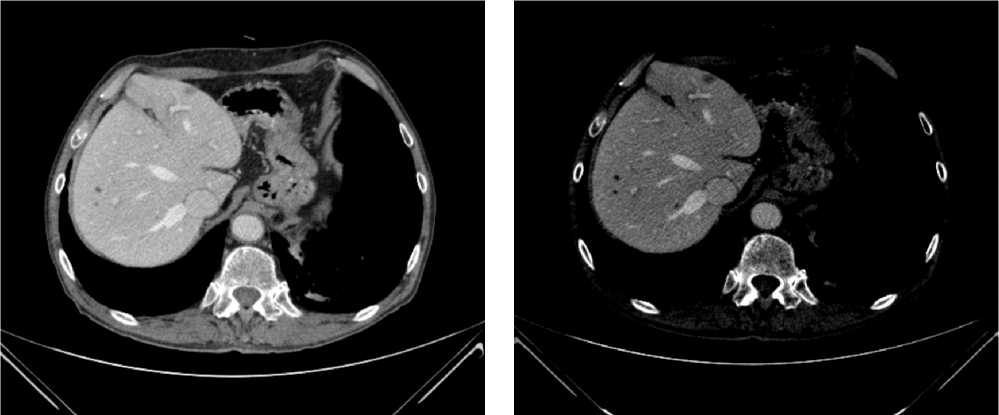

При КТ органов брюшной полости и магнитно-резонансная томография (МРТ) органов малого таза (ОМТ) от августа 2022 г. визуализированы патологические образования в печени метастатического характера (n = 8), расположенные билобарно, и образование средне/верхнеампулярного отделов прямой кишки mrT3d/T4aN2 (CRM+ за счет прилежания лимфатического узла/EMVI+). По результатам молекулярно-генетического исследования обнаружена мутация G13D в 13 кодоне гена KRAS.

Диагноз был установлен как рак среднеампулярного отдела прямой кишки сТ4аN2M1 (hep).

По решению онкологического консилиума пациенту начат ПХТ 1 линии в режиме FOLFOX + бевацизумаб. С 02.09.2022 проведено 3 цикла ПХТ 1 линии, по результатам контрольных обследований зарегистрировано прогрессирование процесса за счет роста образований печени до 64 × 46 мм и появления линзовидного образования между передней поверхностью прямой кишки и задней поверхностью предстательной железы размерами 47 × 15 × 25 мм (рис. 7, 8).

Рис. 7. Результаты компьютерной томографии органов брюшной полости у пациента 37 лет с диагнозом метастатический колоректальный рак с признаками микросателлитной нестабильности (октябрь 2022 г., после 3-х циклов FOLFOX + бевацизумаб)

Fig. 7. Results of abdominal CT scan in a 37-year-old patient diagnosed with metastatic MSI-H colorectal cancer (October 2022, after 3 cycles of FOLFOX + bevacizumab)

Рис. 8. Результаты магнитно-резонансной томографии органов брюшной полости у пациента 37 лет с диагнозом метастатический колоректальный рак с признаками микросателлитной нестабильности (октябрь 2022 г., после 3-х циклов FOLFOX + бевацизумаб)

Fig. 8. Results of abdominal MRI in a 37-year-old patient diagnosed with metastatic MSI-H colorectal cancer (October 2022, after 3 cycles of FOLFOX + bevacizumab)

В октябре 2022 г. получены результаты иммуногистохимического исследования на предмет MSI, выявлена утрата ядерной экспрессии MLH1 и PMS2.

С учетом результатов ИГХ, прогрессирования процесса по результатам контрольных обследований, пациенту начата 2 линия системного лечения пембролизумабом в монорежиме.

С ноября 2022 г. выполнено 14 введений пембролизумаба с максимальным эффектом частичный регресс (образование между передней поверхностью прямой кишки и задней поверхностью предстательной железы регрессировало полностью). По результатам контрольных обследований (КТ ОБП и МРТ ОМТ от сентября 2023 г.) сохраняются очаги в печени до 21 × 11 мм, а также опухоль средне- и верхнеампулярного отделов прямой кишки с выраженным муцинозным компонентом. МР-стадия Т4а (CRM+, EMVI+) (рис. 9, 10).

Рис. 9. Частичный регресс, по данным компьютерной томографии органов брюшной полости, на фоне иммунотерапии пембролизумабом у пациента 38 лет с диагнозом метастатический колоректальный рак с признаками микросателлитной нестабильности (сентябрь 2023 г.)

Fig. 9. Partial response according to abdominal CT scan data during immunotherapy with pembrolizumab in a 38-year-old patient with metastatic MSI-H colorectal cancer (September 2023)

Рис. 10. Частичный регресс, по данным магнитно-резонансной томографии органов брюшной полости, на фоне иммунотерапии пембролизумабом у пациента 38 лет с диагнозом метастатический колоректальный рак с признаками микросателлитной нестабильности; МР-стадия Т4а (CRM+, EMVI+) (сентябрь 2023 г.)

Fig. 10. Partial response according to abdominal magnetic resonance imaging during immunotherapy with pembrolizumab in a 38-year-old patient diagnosed with metastatic MSI-H colorectal cancer; MR stage T4a (CRM+, EMVI+) (September 2023)